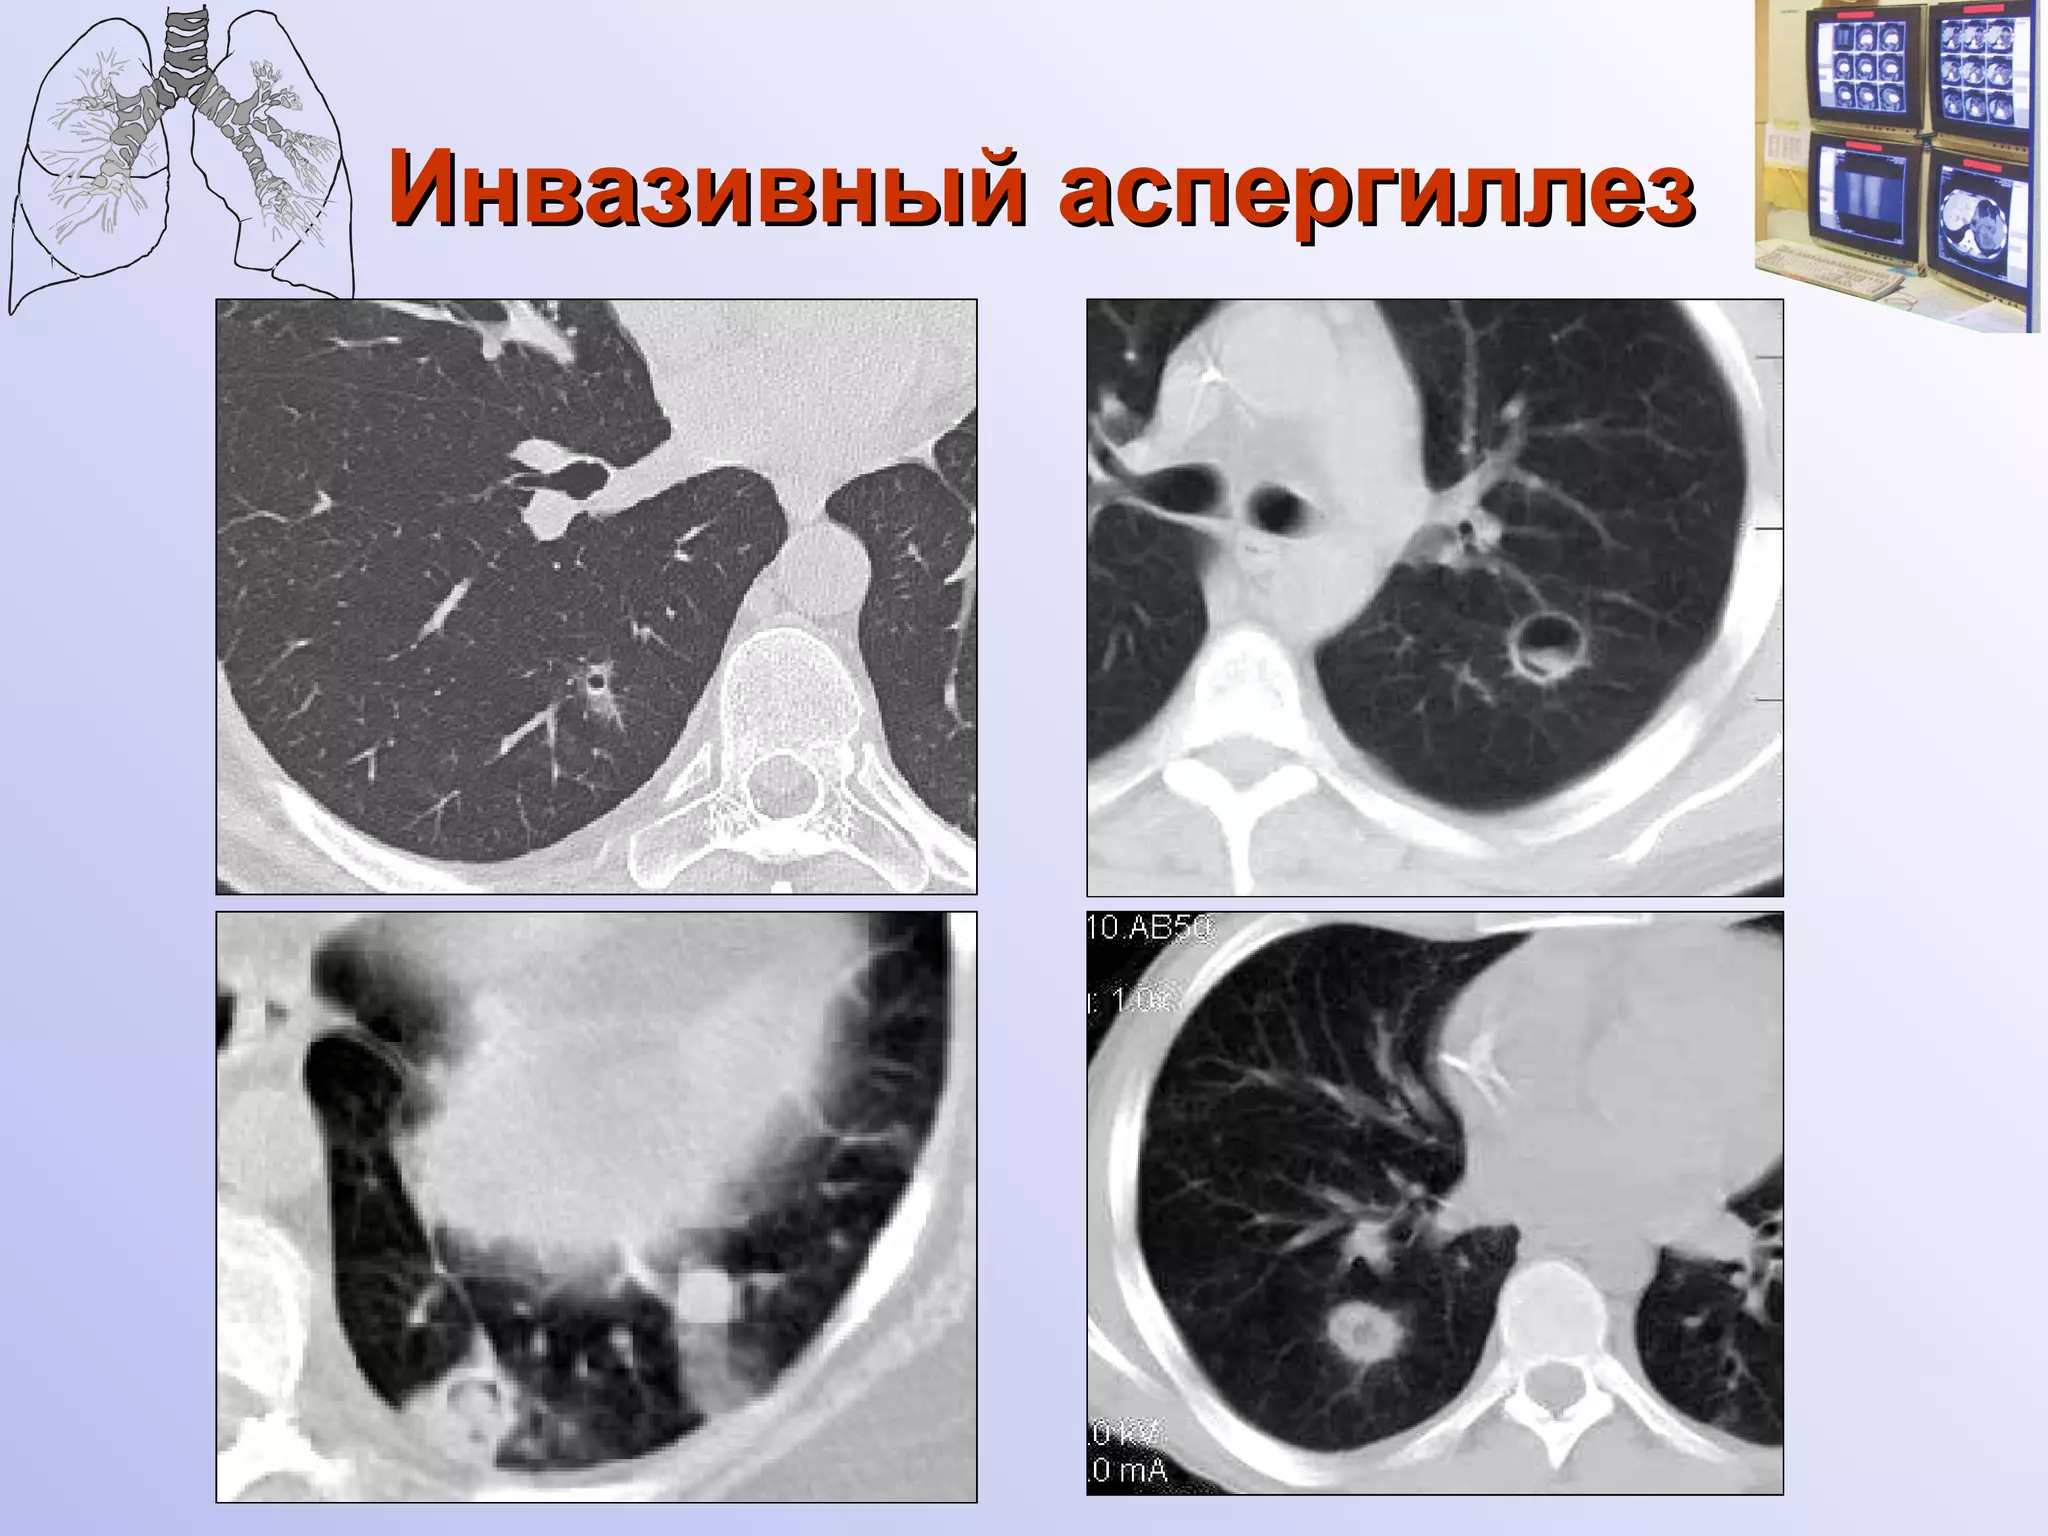

Инвазивный аспергиллез

Инвазивный аспергиллез легких

Инвазивный аспергиллез Множественные аспергилломы

Инвазивный аспергиллез Диссеминированная форма

Инвазивный бронхолегочный аспергиллез  Полостная форма 91,7% Диссеминированная форма 8,3% Рентгенологически значимый признак –   наличие полостных образований ( 91,7%  случаев)